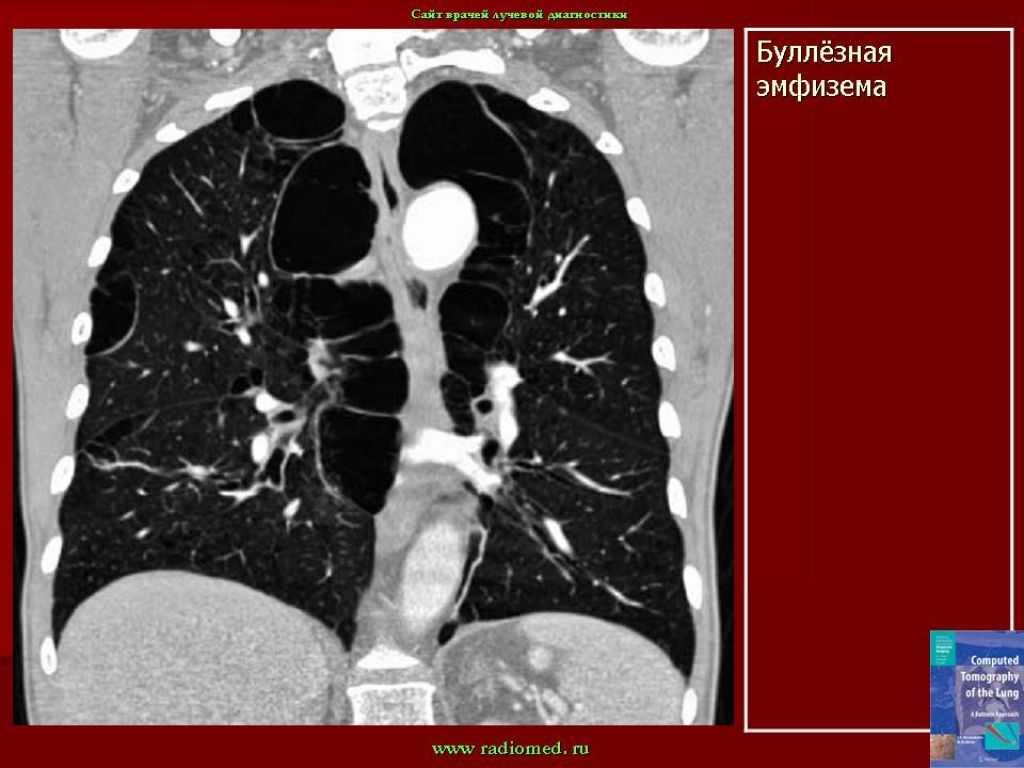

Буллёзная эмфизема лёгких — это заболевание, при котором в лёгких образуются большие воздушные пузыри, или буллы, что приводит к ухудшению дыхательной функции. Эта статья предоставляет полное руководство по пониманию и лечению этого состояния, а также полезные советы для пациентов и их семей.

Буллезная эмфизема легких